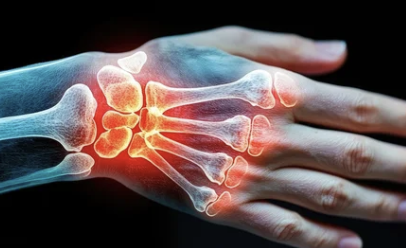

- 관절 부위가 붓고 열감이 느껴진다.

- 관절이 변형되고, 움직임이 제한된다.